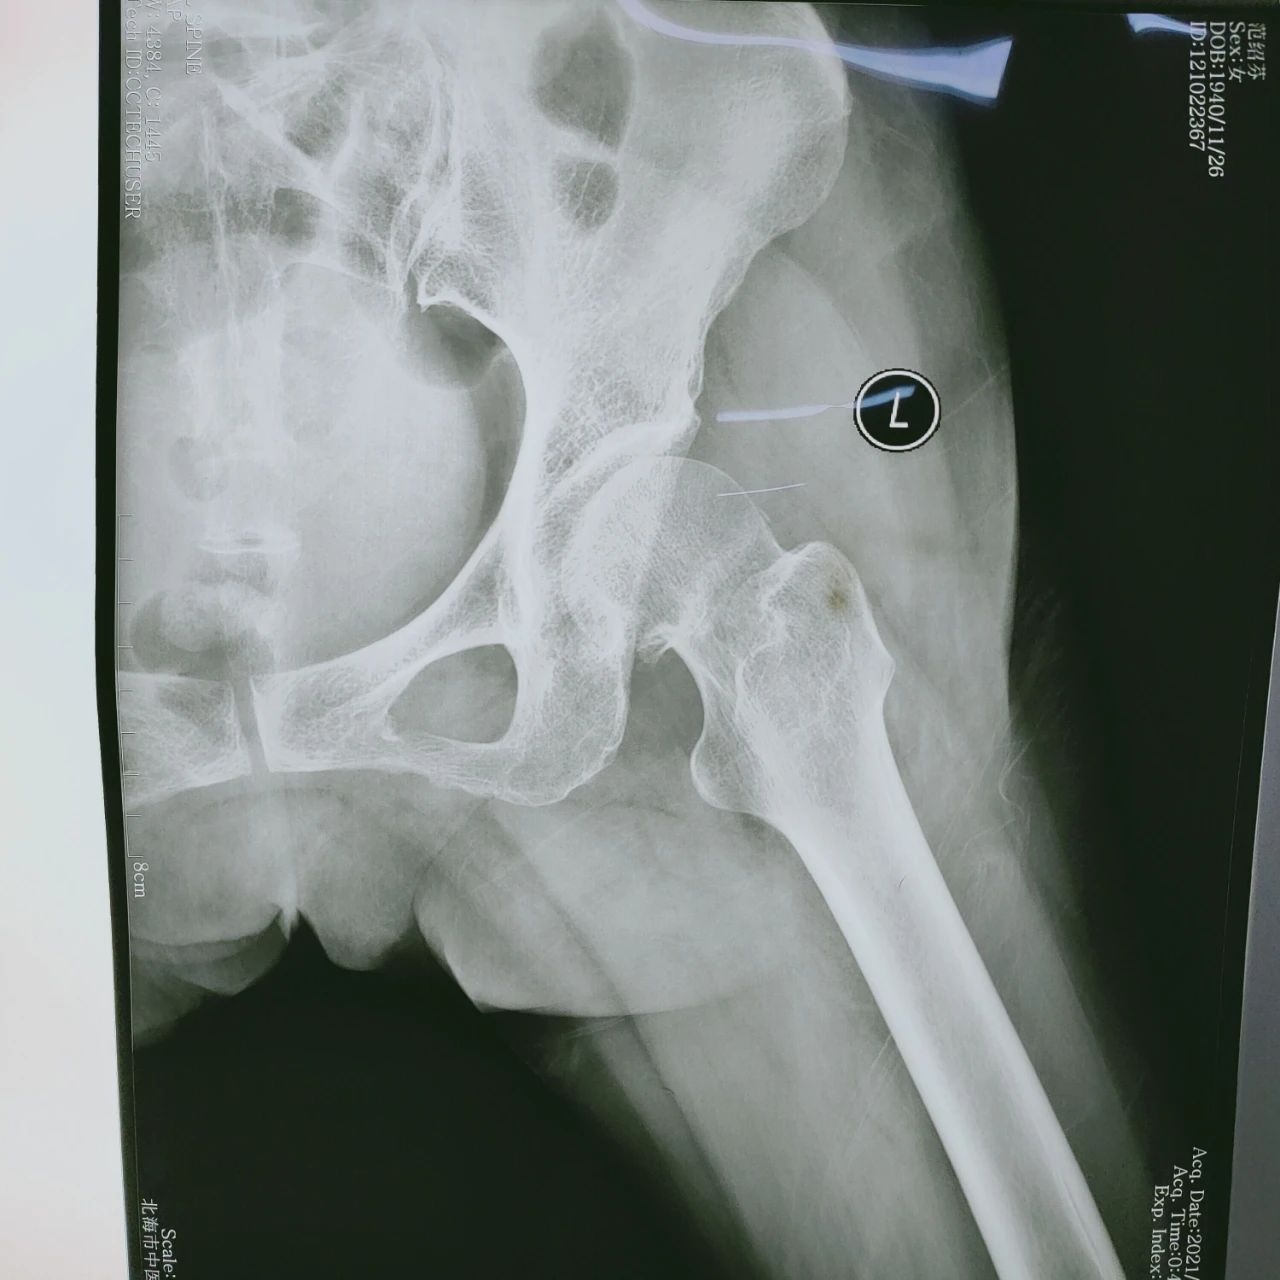

患者为80岁老年女性,因跌伤致股骨颈骨折而入院。因该病人为高龄患者,且长期患有高血压等基础疾病及机体功能退变,如果选择非手术治疗方案,患者需要卧

床长达3-6个月时间,容易并发肺炎、泌尿系统感染等。为了使患者能够尽快恢复肢体功能,提高生活质量,骨伤科二病区专家经讨论,为患者制定了实施微创髋

关节置换手术的方案。通过完善相关检验检查,排除手术禁忌症,经过充分术前准备,给予患者行SuperPath微创髋关节置换术。手术由副院长、主任医师